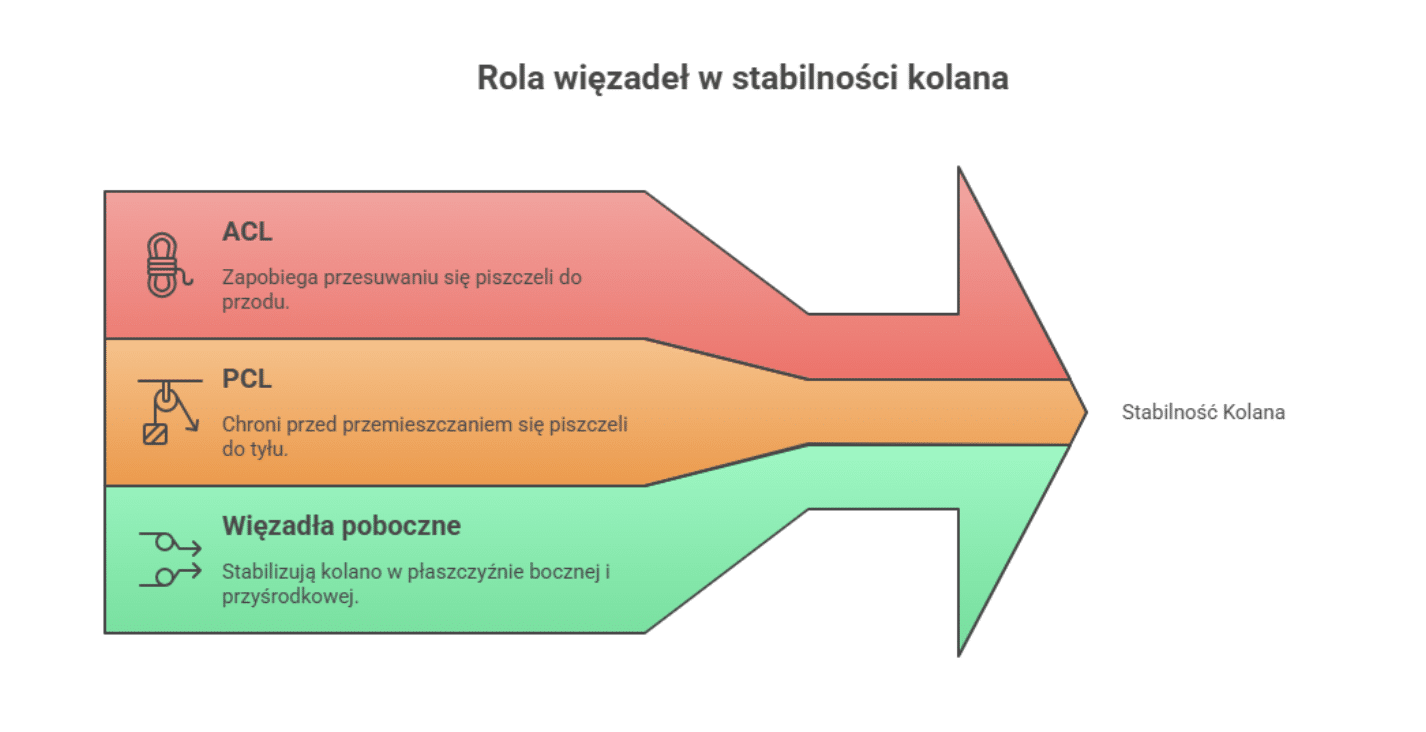

W obrębie kolana wyróżniamy kilka głównych więzadeł:

- więzadło krzyżowe przednie (ACL),

- więzadło krzyżowe tylne (PCL),

- więzadło poboczne przyśrodkowe (MCL),

- więzadło poboczne boczne (LCL),

- więzadło rzepki.

Każde z nich pełni odrębną, ale równie istotną rolę. ACL zapobiega nadmiernemu przesuwaniu się kości piszczelowej względem kości udowej do przodu oraz ogranicza ruchy rotacyjne, co jest szczególnie ważne podczas gwałtownych zmian kierunku ruchu. PCL chroni przed przemieszczaniem się piszczeli do tyłu, natomiast więzadła poboczne stabilizują kolano w płaszczyźnie bocznej i przyśrodkowej, zabezpieczając je przed niekontrolowanymi wychyleniami na boki.